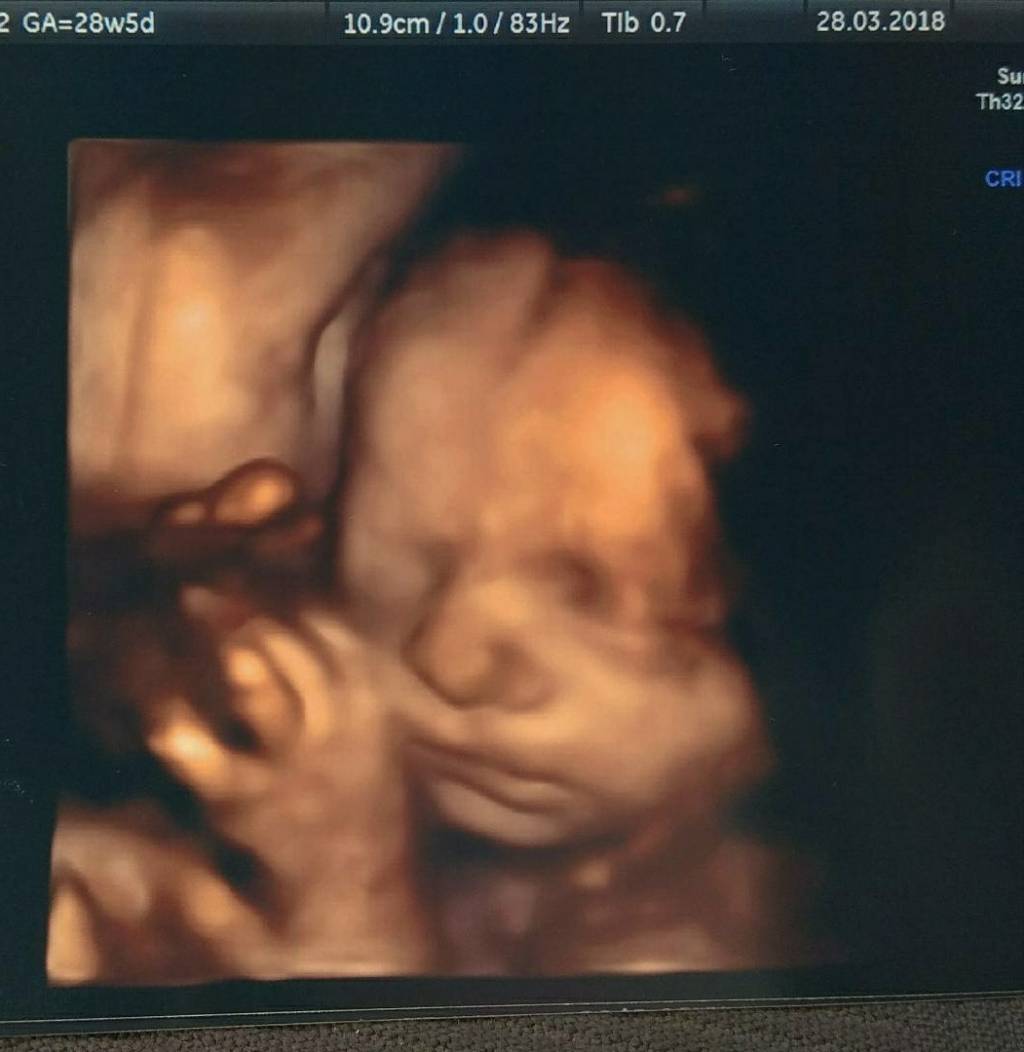

Cudo ❤❤❤ile bym dala zeby moja kruszynka juz taka bylaHaha! Gratuluję. A to moja blada kreseczkaZobacz załącznik 845624

Ktory to juz tydzien ?Haha! Gratuluję. A to moja blada kreseczkaZobacz załącznik 845624

To było w 29Ktory to juz tydzien ?

Syn. Mimo, że brzuch już widoczny, czuje ruchy regularnie to czasem nadal nie dowierzam, że będę mamą... Coś pięknegoBedzie dobrze zobaczyszcorunia czy synus ?